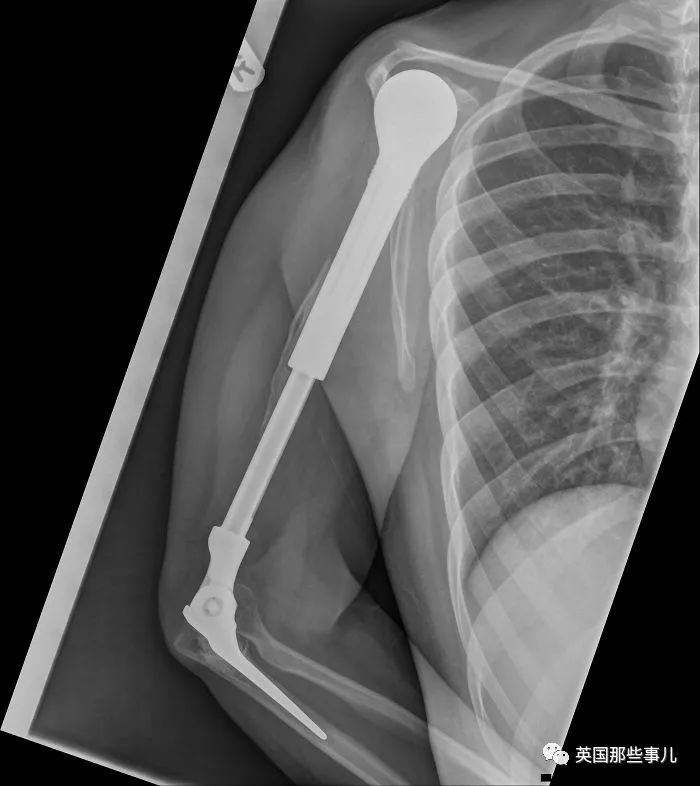

我有一條金屬臂